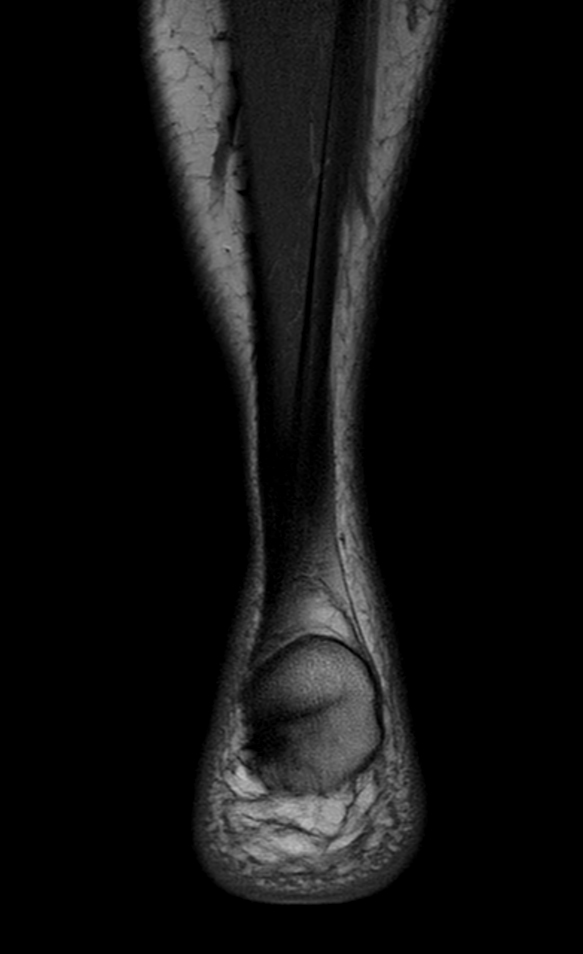

Imaging with the dS 16ch FootAnkle coil

General Hospital Sint Blasius, Dendermonde, Belgium

Patient who was referred for imaging of the achilles tendon